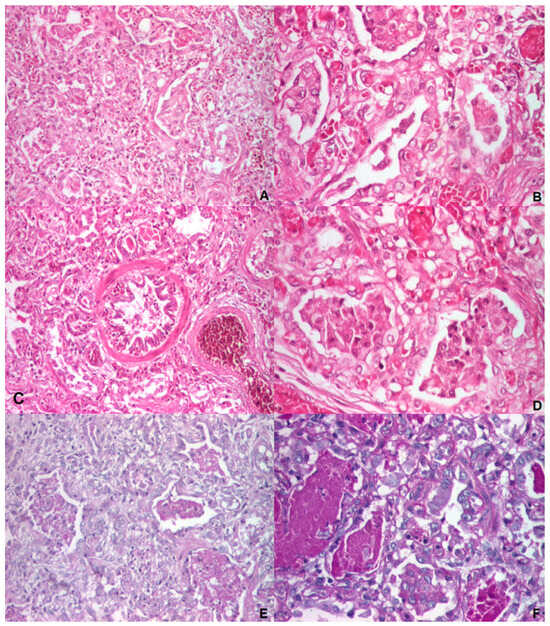

3.1.4. Autopsy and Histology

| 10. | Ognean et al., 2024 (this study) | Male | 37 weeks | 2700 g | Severe nRDS—advanced respiratory support (HFOV), prednisone, azithromycin, hydroxychloroquine treatment | Thoracic X-ray—ground glass homogeneous opacity | CPI pattern with lobular remodeling, prominent AEC II hyperplasia, focal PAP pattern, and extensive DIP-like areas; alveolar proteinosis | N/A | p.Arg280Cys (R280C, c.838C>T, rs201299260)/heterozygous/paternal origin | p.Gln233ter (Q233X, Q233*)heterozygous/maternal origin | SFTPB p.Val267Ile | No, healthy parents, one healthy sibling despite carrying p.Gln233ter and SFTPB p.Val267Ile variants | Died at 77 days of life | Current case report |